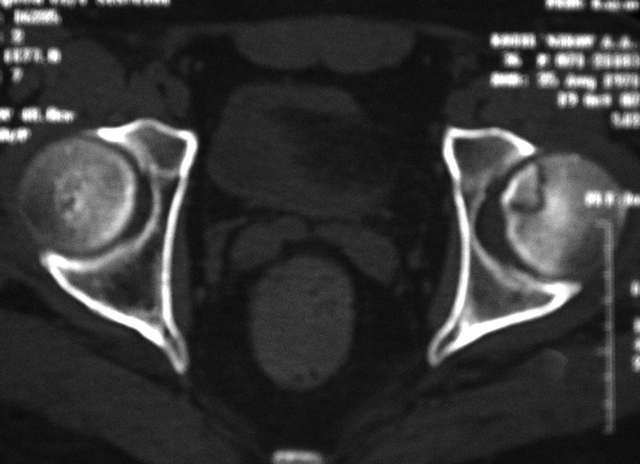

Молодой человек, 37л. Начало заболевания сентябрь 2007, резкие боли в области лев. тазобедренного сустава, повышение температуры до 39 гр., в течение недели, лабораторные данные: лейкоцитоз со сдвигом влево. Посев крови на стерильность возбудителя не выявил. По данным Рг, РКТ выставлен диагноз: Левосторонний коксит? Асептический некроз? Проводилось лечение: цефсон в/в неделю, иммобилизация кокситной повязкой 1 мес. Обратился повторно 10 дней назад с жалобами на сильные боли в левом тазобедренном суставе, белая кровь – нормограмма, СОЭ 46 мм/ч. На сегодняшний день: болей не отмечает. Лаб.данные: белая кровь – нормограмма, СОЭ 30 мм/ч. Рентген и РКТ прилагаем.

Мне представляется, что предоставлен случай аваскулярного некроза головки бедра. Для определения тактики лечения необходимо выполнить ренгенограммы лучшего качества и посмотреть все срезы на уровне головки. Предоставленные срезы -уровень ямки,т.е. малонагружаемой зоне, наличие в этой зоне участков сегментарного некроза скорее всего не приведет к деформации головки, при таком варианте разгрузка конечности на 3-4 мес может привести к благоприятному исходу.

При наличии участков некроза внутри головки близко к нагружаемой зоне для профилактики имперссионного прелома, вероятно, целесообразно выполнить Core Decompression (тема обсуждалась на форуме). В случае расположения участков некроза, затрагивающих суставную поверхность в нагружаемой зоне может быть целесообразным выполнение операций на проксимальном отделе бедра, ставящих целью выведение участков некроза из под нагрузки. Ну и протезирование, конечно, как вариант.